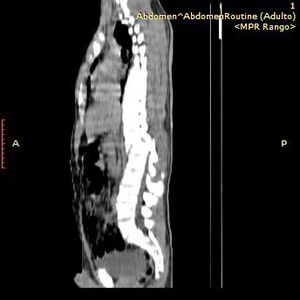

Diagnostic? 😱

Tomography

Spine

Spinal

Medula

Fractur vertebra thoracal 11-12